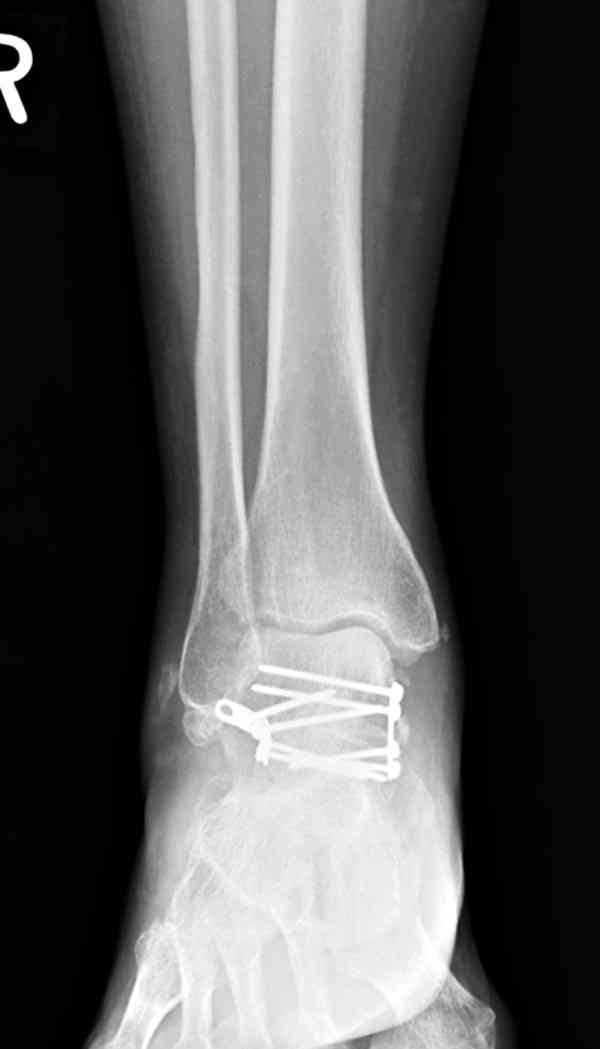

Случай с множественным оскольчатым переломом тарана оперированный из двойного доступа.

Через 2 мес.:

Через 8 мес.:

Через 14 мес.:

И второй случай из недавней ташкентской практики, (извините за качество ренгенограммы и только в одной проекции) случай падения с высоты (кстати моего друга - известного киноактера) - открытый

смещенный перелом тарана, с переломом переднего края дистального эпиметафиза большеберцовой кости.

При поступлении в приемной сделана первичная обработка с ушиванием открытой латеральной раны и вытяжением за пятку.

Из-за отсутствия времени пришлось оперировать на второе утро, из материала, что имеем на месте, фиксирован двумя шурупами, а третий-это контур сломанного жойстика в 4 мм. На дистальный медиальный конец тибиа antiglide 3.5 мм пластина. Через пару дней выписан и несмотря на предупреждение, самостоятельно начал нагрузку в 4 недели, время не ждет, снимается в боевике в Росийской Федерации.

Решили не связываться с остеосинтезом, а сделать сразу берцово-пяточный блок. Снимки в приложении.

По завершении удлинения, наверно, заштифтуем.

Комментарии/критика приветствуются.